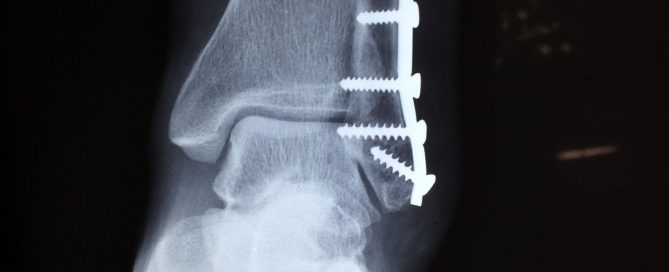

Infection nosocomiale Le 12 avril 2006, un homme approchant la soixantaine, exerçant l’activité de mécanicien monteur, est victime d’un accident du travail. Il souffre d’une fracture fermée complexe à sa cheville gauche. Hospitalisé en clinique, il est pris en charge par un médecin exerçant à titre libéral qui pratique une ponction au niveau du site traumatique … Lire la suite de Perte de gains professionnels futurs de la victime d’une infection nosocomiale devenue inapte à l’emploi